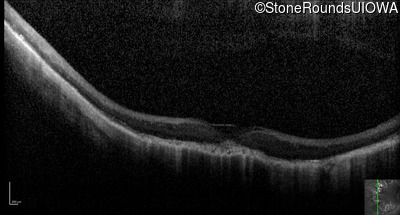

Optical Coherence Tomography - Left - 5/200

Exemplar / OCT Stack

OCT Stack